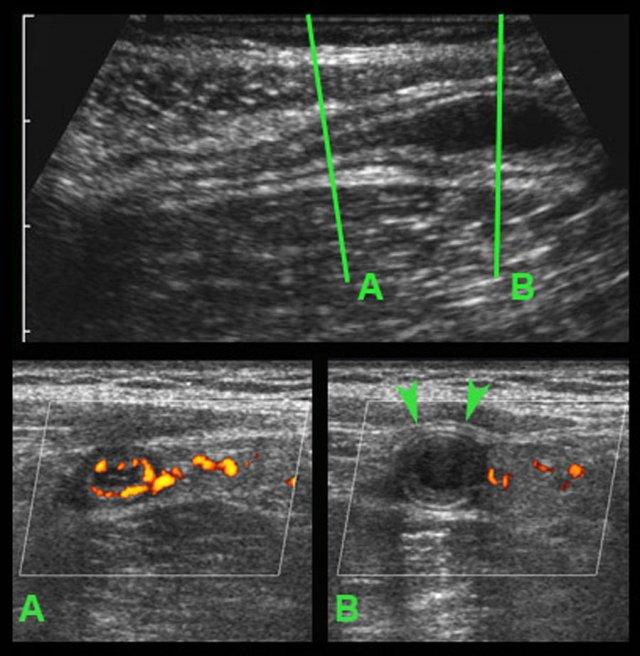

Ở bệnh nhân rất gầy này với viêm ruột thừa cấp giai đoạn sớm, siêu âm cho thấy hình ảnh giãn đoạn xa của ruột thừa.

Trên mặt phẳng A, siêu âm Doppler cho thấy tình trạng tăng sinh mạch máu mạnh ở thành ruột thừa; tuy nhiên trên mặt phẳng B, không quan sát thấy mạch máu trong thành ruột thừa do áp lực trong lòng cao.

Lưu ý hình ảnh ruột thừa giãn, tròn, không thể ép xẹp trong mặt phẳng B, phồng vào thành bụng khi ấn (đầu mũi tên), với tín hiệu mạch máu chỉ còn ở vùng mạc treo ruột thừa có mỡ xung quanh.